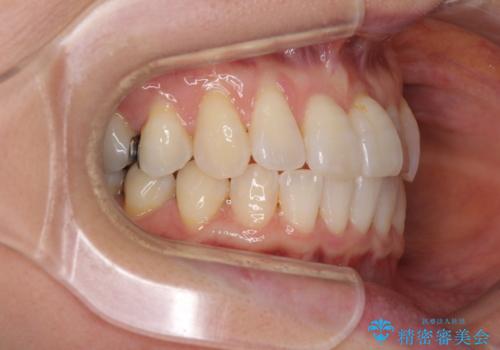

前歯のクロスバイト インビザライン矯正で改善

- むし歯治療を契機に、長年気にしていた前歯のクロスバイトの改善を希望された患者様です。

汚れが溜まりやすく、歯ぎしりがうまくできないため、インビザラインを用いて矯正治療を行うこととしました。

インビザラインによる前歯のクロスバイトの改善は、治療期間中に前歯でしか咬めない時期が続いたり、歯肉退縮や歯髄壊死のリスクが高まったりと、治療中にトラブルを抱えることがあります。

特に上顎側切歯(真ん中から2番目の歯)が舌側に引っ込んでいるケースは、インビザラインでは改善しきれないことがあると言われています。